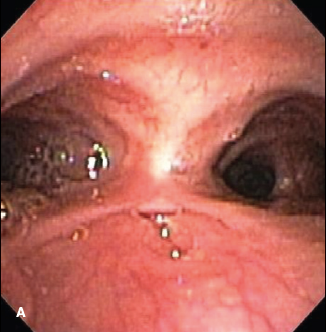

Gregory W. Rutecki, MD

<p><strong><em><img alt="dieulafoy lesion" height="90" src="/sites/default/files/images/Screen%20shot%202012-10-12%20at%2010.15.57%20AM.png"...